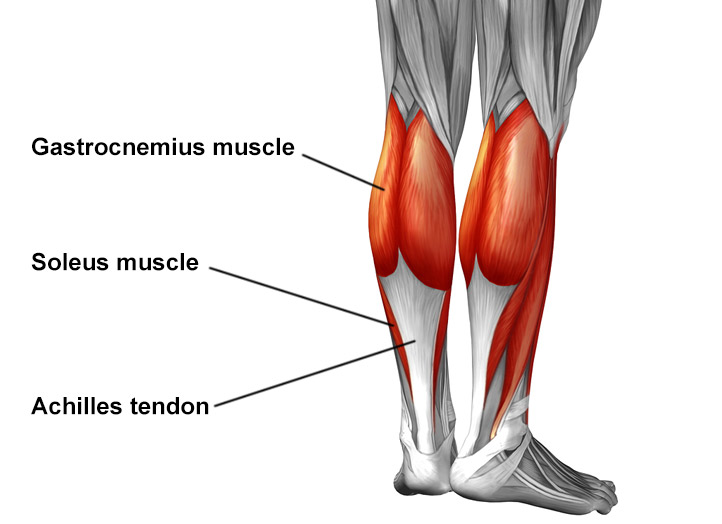

A tendinite de Aquiles é aquela dor chata que aparece na parte de trás do seu calcanhar, bem ali onde o músculo da panturrilha se liga ao osso do pé. Sabe, é uma inflamação desse tendão forte que usamos para correr, pular e até para andar. Quando exigimos demais dele, ou quando ele já está cansado e fraco, o problema aparece.

Quando falamos de fortalecimento, não estamos falando de levantar pesos enormes de cara. Começamos com exercícios mais leves e focados, que visam principalmente a panturrilha (músculo gastrocnêmio e sóleo). Eles são os grandes responsáveis por fazer o movimento do nosso pé lá atrás. Exercícios como elevação de calcanhar, tanto com os joelhos esticados quanto dobrados, são essenciais. Fazer de forma controlada e com atenção à sua resposta corporal é fundamental para não sobrecarregar ainda mais o tendão que já está sensível.